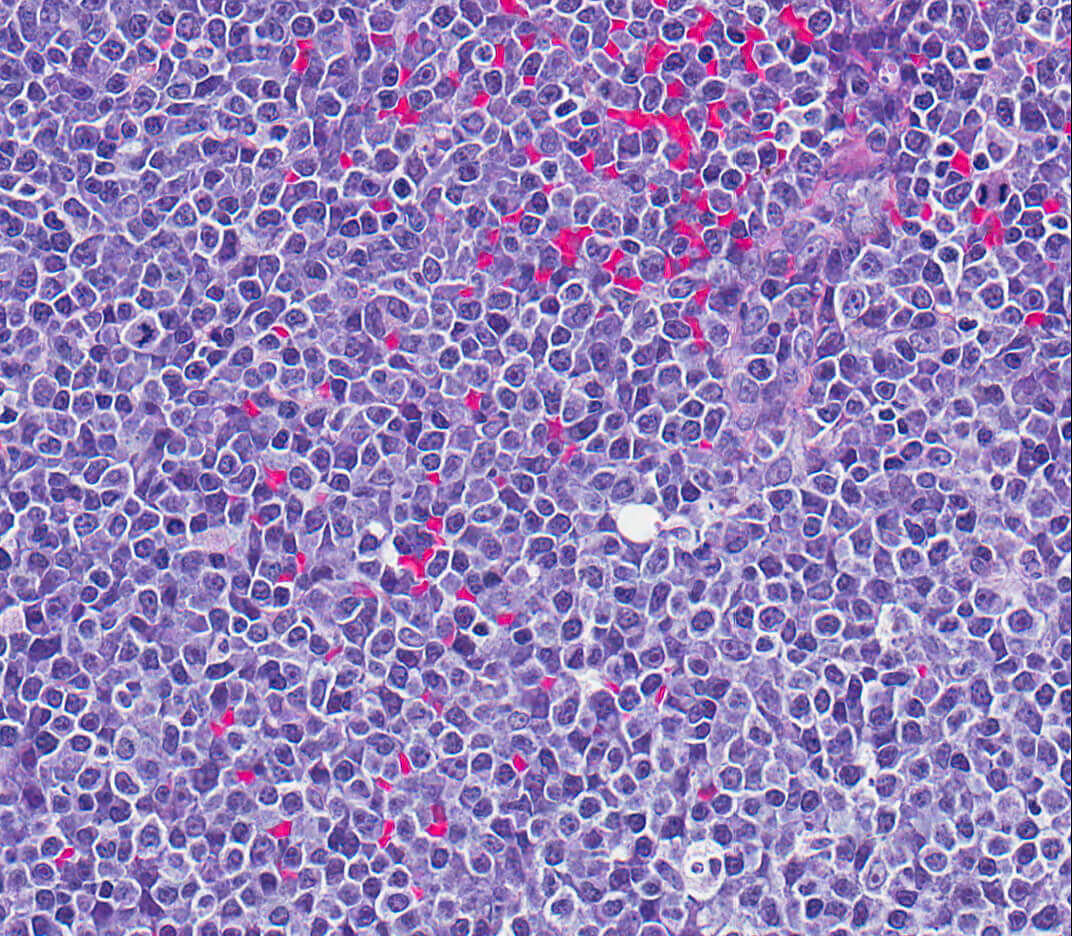

tissue architecture This image shows a histopathologic section, viewed under 40X microscopy, with the overview of the tissue architecture of diffuse large B-cell lymphoma. The image was provided by the Purdue University Collaborative Core for Cancer Bioinformatics (C3B), which brings together Purdue and Indiana University scientists to find data-driven solutions. Download image

C3B scientists explore diverse biological big data to perform different analyses, such as identifying mutations in the genome or gene expression patterns that may be associated with or cause a specific type of cancer. The C3B collaborated with Purdue faculty members Mike Childress, John Turek and David Nolte on a project that uses pet dogs with naturally occurring diffuse large B-cell lymphoma (DLBCL) as a model for studying chemotherapy resistance in lymphoma patients.

DLBCL is an aggressive form of non-Hodgkin’s lymphoma and half of patients diagnosed with the disease will die because of the development of chemotherapy resistance.  The project combined gene mutation data, gene expression data and data from a technique, biodynamic imaging (BDI), developed by Nolte and Turek, which performed phenotypic profiling of three-dimensional tissue samples.